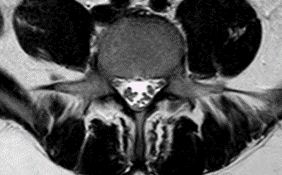

Se toman imágenes de control observando progresión de processo inflamatório a nível cerebral y a nível lumbar (figuras 4 y 5), progresión de siringomielia com afectación a nível cervical (figura 6)

Mayor agrupamento de raíces a nível lumbar.

Figura 5